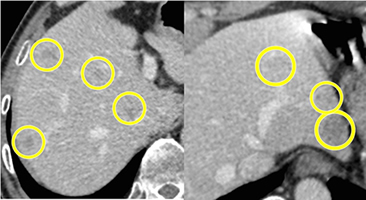

上図も転移性肝臓がんの手術前のCTですが、黄色の丸で囲ってある部位に腫瘍が存在します。この症例では肝臓の左右に腫瘍が多発していました。